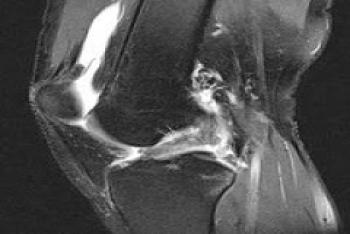

![Ön Çapraz Bağ]()

Ön Çapraz Bağ

Omuz 16205 OkunmaÖn Çapraz Bağ

Ön Çapraz Bağ Yaralanmalarını okumak için tıklayınız.Ön Çapraz Bağ Cerrahi Animasyonunu seyretmek için tıklayınız.Ön Çapraz Bağ Cerrahisi Sonrası ...